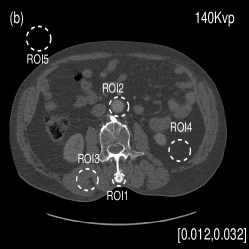

We acquired the Catphan©600 phantom data on a tabletop cone-beam CT (CBCT) system whose geometry matched that of a Varian On-Board Imager (OBI) on the Trilogy radiation therapy machine. We inserted iodine solutions with nominal concentrations of and into the phantom. There were pixels with a physical size of per pixel on the CB4030 flat-panel detector (Varian Medical Systems). The DECT measurements were obtained at kVp and kVp with a tube current of mA and a pulse width of ms. We acquired projections over in each scan. Using a fan-beam geometry with a longitudinal beam width of on the detector niu2010shading , We acquired projections with scatter contamination inherently suppressed. We used a contrast rod slice of the Catphan©600 phantom to evaluated the proposed method. We reconstructed attenuation images of size with a pixel size of . Fig. 3 shows the low- and high-energy CT images. Fig. 3(a) identifies the rods with labels: Teflon (labeled as ), Delrin (labeled as ), Iodine solution of (labeled as ), Polystyrene (labeled as ), low-density Polyethylene (LDPE) (labeled as ), Polymethylpentene (PMP) (labeled as ), Iodine solution of (labeled as ). Fig. 3(b) shows selected basis materials and ROIs in white dashed line circles: Teflon (ROI1), Delrin (ROI2), Iodine solution of (ROI3), PMP (ROI4), Inner soft tissue (ROI5) and Air (ROI6).

We also evaluated the proposed PWLS-TNV- method using clinical pelvis data. The patient’s pelvis data was acquired by Siemens SOMATOM Definition flash CT scanner using DECT imaging protocol. Table 4 lists acquisition parameters in the pelvis data scan. Fig. 5 shows the high- and low-energy CT images of the pelvis data. Fig.5 (b) shows selected basis materials, bone, iodine, muscle, fat and air, and their assosicated ROIs highlightened in white dashed line circles. We implemented the Direct Inversion method in mendonca2014a and used its results as the initialization for the PWLS-EP-LOOP xue2017statistical and the proposed PWLS-TNV- method. Fig. 6 shows the decomposed material images by the Direct Inversion, the PWLS-EP-LOOP and the PWLS-TNV- method. Table 5 summarizes the means and noise STDs of the decomposed material images by the above three methods. The volume fraction (VF) accuracies are , , and for the Direct Inversion method, the PWLS-EP-LOOP method and the proposed PWLS-TNV-, respectively. Compared with the Direct Inversion and PWLS-EP-LOOP method, the proposed method improves the VF accuracy by and respectively. The proposed PWLS-TNV- method decomposes basis material images more accurately, suppresses noise and decreases crosstalk, while retaining spatial resolution of the decomposed images compared to the other two methods.